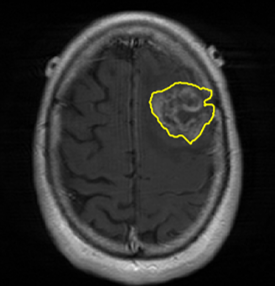

We argue that the sub-optimal paradigm of processing different abstractions within a single CNN pipeline can be remedied through the effective processing of information in a structured manner. Consequently, we devise strategies for disentangling the edge and texture information within a single training pipeline. Figure 2 illustrates how our proposed module, dubbed EG-CNN, can be paired with any existing CNN encoder-decoder to improve segmentation quality near intensity edges. We have applied our EG-CNN to the tasks of brain and liver tumor segmentation in medical images (Figure 3).

(1) Brain MR (2) Liver MR (3) Liver CT (4) Lung CT

Edge-Aware 2D Image Segmentation Networks

[49; 48]: Fully convolutional neural networks (CNNs) have proven to be effective at representing and classifying textural information, thus transforming image intensity into output class masks that achieve semantic image segmentation. In medical image analysis, however, expert manual segmentation often relies on the boundaries of anatomical structures of interest. We propose 2D edge-aware CNNs for medical image segmentation. Our networks are designed to account for organ boundary information, both by providing a special network edge branch and edge-aware loss terms, and they are trainable end-to-end. We validate their effectiveness on the task of brain tumor segmentation using the BraTS 2018 dataset. Our experiments reveal that our approach yields more accurate segmentation results, which makes it promising for more extensive application to medical image segmentation. -

Plug-and-Play Edge-gated 3D Image Segmentation Networks

[50]: We propose a plug-and-play module, dubbed Edge-Gated CNNs (EG-CNNs), that can be used with existing encoder-decoder architectures to process both edge and texture information. The EG-CNN learns to emphasize the edges in the encoder, to predict crisp boundaries by an auxiliary edge supervision, and to fuse its output with the original CNN output. We evaluate the effectiveness of the EG-CNN against various mainstream CNNs on the publicly available BraTS19 dataset for brain tumor semantic segmentation, and demonstrate how the addition of EG-CNN consistently improves segmentation accuracy and generalization performance. -